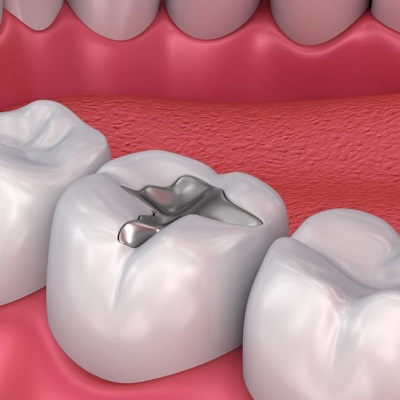

Tooth fillings are a common dental solution used to restore the structure and function of a damaged tooth. However, there are instances where a filling might come loose or even fall out. If this happens, it’s essential to know the steps to take to avoid further damage to your tooth. Visiting the Best Dental Tooth Filling Clinic In Dubai is crucial to ensure you receive prompt and professional care. But first, let's explore why fillings fall out and what actions you can take if it happens to you.

Several factors can lead to the dislodgement of a tooth filling. Fillings are meant to last for several years, but they can become loose due to:

Over time, the constant pressure from chewing, grinding, and clenching can wear down a filling. The Best Dental Tooth Filling Clinic in Dubai uses high-quality materials to ensure longevity, but wear and tear are inevitable for older fillings.

New decay can form around the filling, compromising its structure and causing it to loosen. Regular dental check-ups at the Best Dental Tooth Filling Clinic in Dubai can prevent this issue by catching early signs of decay before it leads to more significant problems.

Chewing on hard substances like ice, hard candy, or pens can damage the filling and cause it to dislodge. Avoiding these habits and visiting a reputable clinic ensures your fillings are well-maintained and long-lasting.

What to Expect at the Best Dental Tooth Filling Clinic in Dubai:

3. Replacement or Repair:

Depending on the condition of the tooth, the dentist will either replace the filling or suggest alternative treatments. At the Best Dental Tooth Filling Clinic in Dubai, you can expect expert care tailored to your dental health needs.